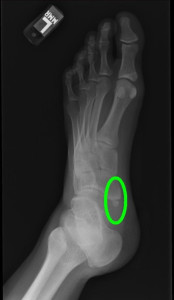

有痛性外脛骨障害

gaikeikotsu